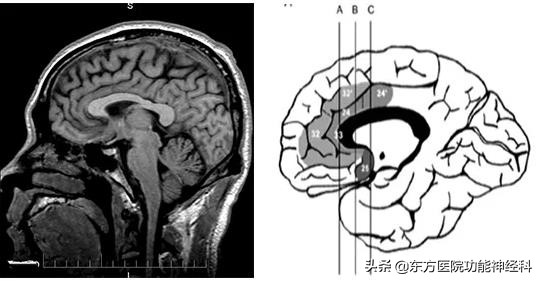

(一)海马环路:Papez环路

1878年法国神经病学家Pierre Pacel Broca注意到扣带回至海马的一圈环节脑结构,组成每侧大脑半球的内侧壁,称之为大边缘叶。1901年Cajal发现扣带回-海马-穹隆为嗅觉的传导通路。Herrick(1993年)认为这一行为、学习和记忆有关。动物试验证明,破坏这些结构可以使动物的行为和情绪发现变化。1937年Papez综合以前的研究资料,提出情感环路理论,即由隔区开始经扣带回至海马,又经穹隆至乳头体,再又乳头体丘脑通路至丘脑前核,最后由前丘脑通路回到扣带回,形成边缘系统的内侧环路,认为此系统可能是情感、感觉和行为中枢,具有协调中枢情感活动的功能。

(一)扣带回位置及毗邻

扣带回绕胼胝体的轮廓走行,从胼胝体下区到压部,构成了扣带回的大部分。经过压部后,在海马回内继续前行,几乎到达颞体。